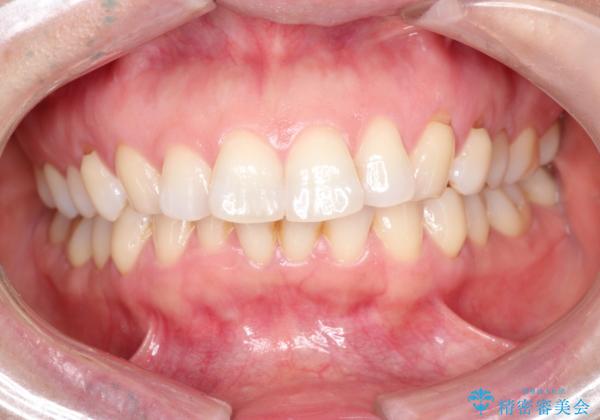

審美装置を用いたワイヤー矯正|非抜歯で歯の凸凹を改善

- 患者様は**歯の凸凹(叢生)**を気にされて来院されました。診査の結果、歯列のスペースが不足しているものの、抜歯をせずに改善できる状態でした。そこで、目立ちにくい審美装置(白いブラケットとホワイトワイヤー)を使用したワイヤー矯正を提案しました。歯列のアーチを広げながら、適宜IPR(歯の幅をわずかに調整する処置)を行い、非抜歯で自然な歯並びへと導く計画を立てました。

治療では、白いブラケットとホワイトワイヤーを使用し、矯正装置が目立ちにくいよう配慮しました。歯列を拡大しながら適切に歯を移動させ、IPRを併用することで、無理なくスペースを確保しました。見た目に配慮しながら、歯の凸凹をスムーズに整え、噛み合わせも改善。患者様からは「装置が思ったより目立たず、歯並びがきれいになって嬉しい」との声をいただきました。